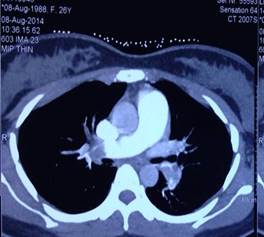

Tắc động mạch phổi cấp được nghi ngờ là nguyên nhân gây sốc, vì bệnh nhân có đau ngực, khó thở, nhịp tim nhanh, có thai 12 tuần và lâm sàng, điện tim có biểu hiện suy tim phải cấp. Chỉ định chụp cắt lớp vi tính (CLVT) động mạch phổi cấp cứu được xem xét. Theo Uỷ ban quốc tế về an toàn phóng xạ (The International Commission of Radiologic Protection), liều tia xạ khi chụp CLVT động mạch phổi phóng qua tử cung người mẹ không làm tăng nguy cơ tử vong hoặc dị tật thai nhi [1]. Bệnh nhân được chụp CLVT 64 dãy động mạch phổi, kết quả cho thấy huyết khối ở cả 2 động mạch phổi phải và trái với mức độ nặng (SI) CLVT là 50%.

Hình 3: Huyết khối ở động mạch phổi phải và trái (SI : 50%)Bệnh nhân được thở oxy, truyền dobutamin tĩnh mạch, dùng heparin bolus và truyền liên tục qua bơm tiêm điện và xem xét dùng thuốc tiêu sợi huyết cấp cứu.